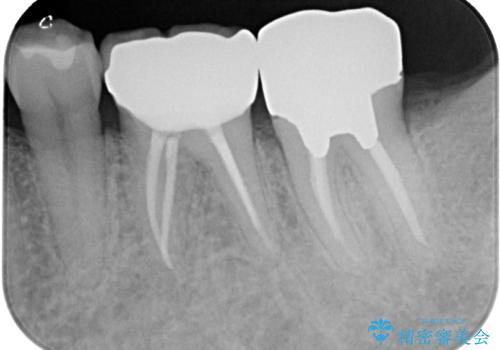

- 下顎大臼歯が噛めないほどの痛みを感じるとのことで来院された患者様です。

レントゲン写真などで診査を行ったところ、不適合な詰め物の周りから炎症が波及し、神経組織が壊死していると診断されました。

まずは根管治療を行い、症状が消退したことを確認してオールセラミッククラウンにて補綴治療を行うこととしました。